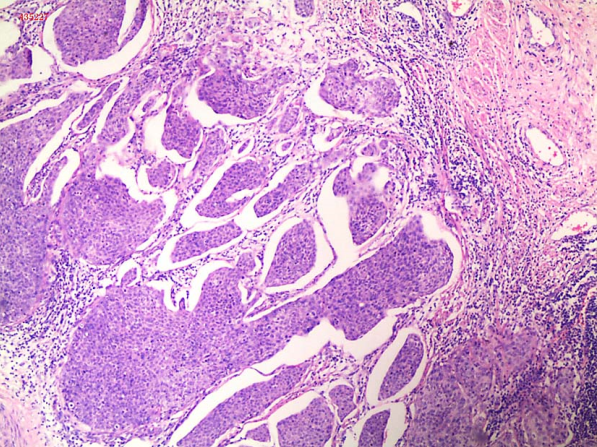

2.腺癌 近年来子官腺癌的发生率有上升趋勢,占子宫颈癌的20%~25%。

(1)巨检:来自子宫管内,浸润管壁;或自子宫颈管内向子宫颈外口突出生长;常可侵犯宫旁组织;病灶向子宫颈管内生长时,子宫颈外观可正常,但因子宫颈管膨大,形如桶状。

(2)显微镜检

1)普通型宫颈腺癌:最常见的组织学业型,约占宫颈腺癌的90%。虽然来源于子宫颈管柱状黏液细胞、偶尔间质内可见黏液池形成,但肿瘤细胞内见不到明确黏液,胞浆双嗜性或嗜酸性。镜下见腺体结构复杂、呈筛状和乳头状,腺上皮细胞增生呈复层,核异型性明显,核分裂象多见。该亚型绝大部分呈高-中分化。

2)黏液性腺癌:该亚型的特征是细胞内可见明确黏液,又进一步分为胃型、肠型、印戒细胞样和非特指型。其中,高分化的胃型腺癌,既往称为微偏腺癌(minimal deviation adenocarcin-oma,MDA),虽然分化非常好,但几乎是所有宫颈腺癌中预后最差的一种亚型,5年生存率仅为普通宫颈腺癌的一半。